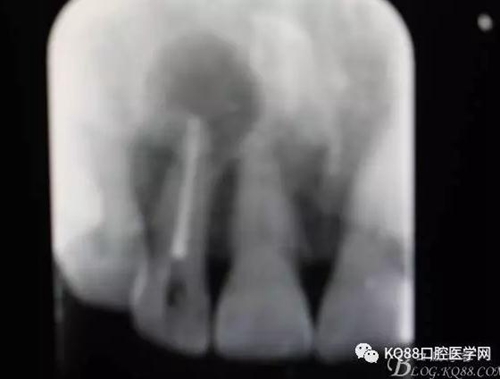

圖2. 12牙齒在我院進(jìn)行熱牙膠根管充填+樹脂充填。

一個月后患者復(fù)查: 唇側(cè)觀:11根尖區(qū)粘膜有一膿瘺,捫診溢膿,牙冠成灰褐色。根管治療無法治愈根尖病變,建議根管外科治療,患者同意手術(shù)。

圖22.術(shù)后的x根尖片影像情況。12根尖區(qū)MTA充填完好。